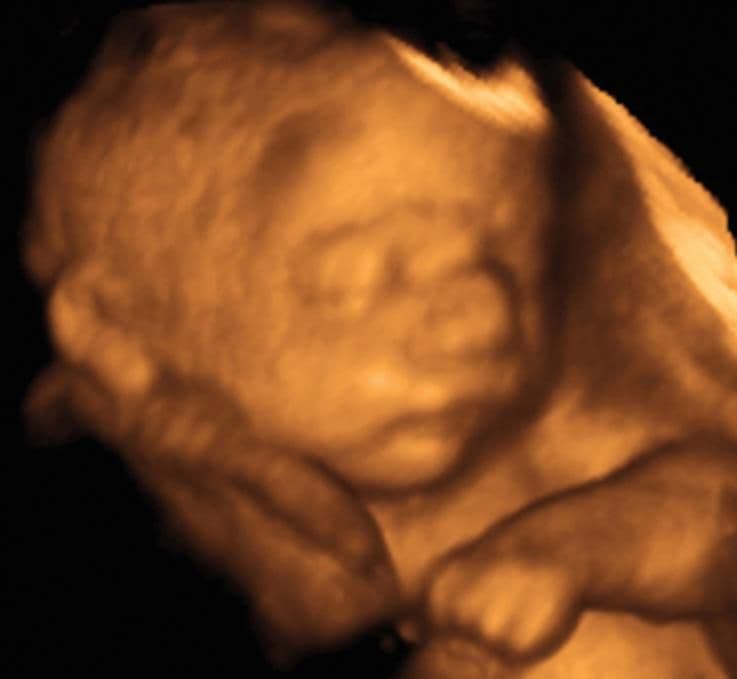

The sleep–wake cycle is now more established, however just because your baby is moving you cannot assume that he is awake. He spends little time fully active with his eyes open, so many of the movements you are feeling are happening while he is asleep.

In the early stages of pregnancy, genetic factors largely determined the size of your baby, but by now environmental factors are becoming more important. Overall, your baby’s final birthweight is determined about 40 per cent by genetic factors and 60 per cent by environmental factors. Your baby grows at a steady rate from 24 weeks until the last 2–3 weeks, when growth continues but more slowly. (If you’re expecting twins, your babies grow as if alone in the uterus up until 28 weeks but from this point there is a reduction in their growth rate.) Your baby’s internal organs account for much of his current growth.The liver and brain, in particular, continue to enlarge and muscle mass increases. Later, fat will be deposited under the skin, rounding out your baby’s contours.